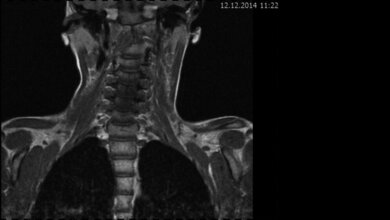

MRT zeigt Tumor

Im Rahmen einer MRT-Untersuchung wurde schließlich ein Tumor gefunden, der auf den Hirnstamm drückte. Nach der Entfernung des Tumors verschwanden die Störungen vollständig.